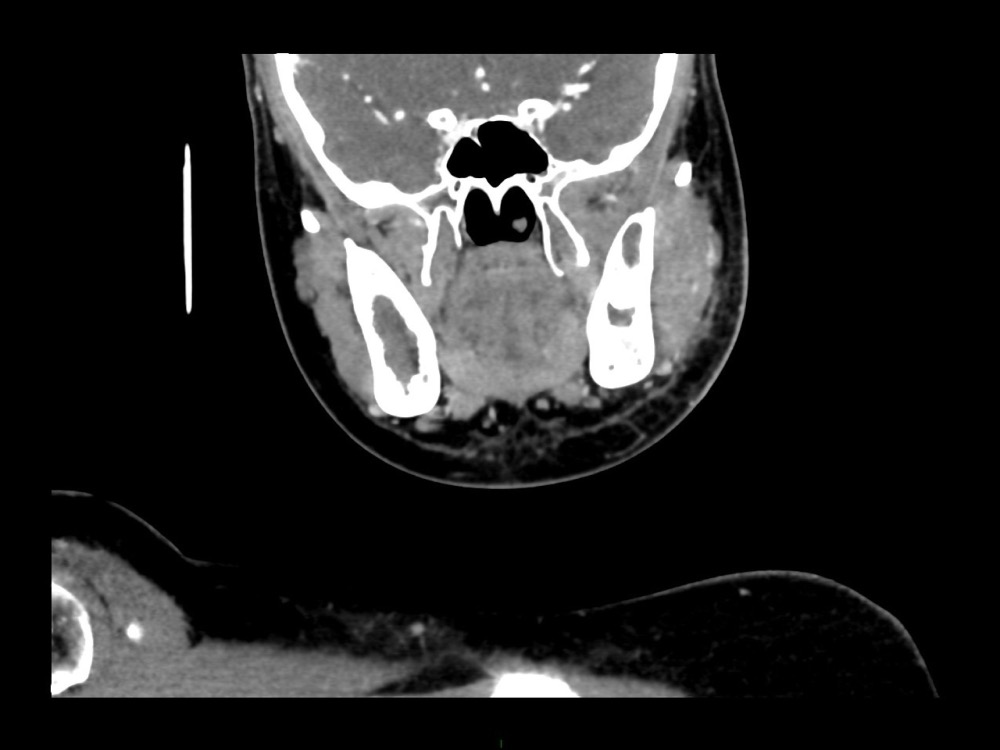

Arsovic / Perrot / Miquel 18/05/2022